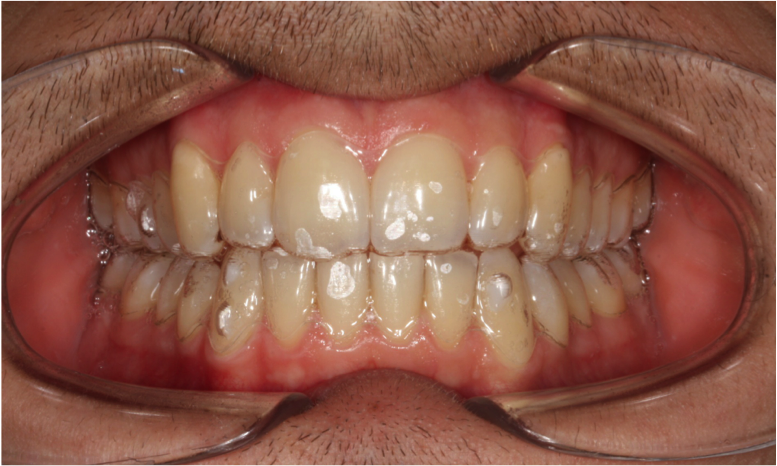

Les appareils fixes (appareils multiattaches communément appelés bagues) que le patient ne peut pas retirer. Ils sont constitués de boîtiers ou verrous collés ou scellés sur les dents, reliés par des fils métalliques dont l’alliage, la section, la forme sont déterminés par les différentes étapes du traitement. Ils peuvent être collées en externe ou en interne.

les attaches ou boitiers métalliques externes,

les attaches ou boitiers esthétiques en céramiques (moins visibles) externes

les appareils utilisés en technique linguale (totalement invisibles). Les techniques linguales offrent la possibilité d’un appareil orthodontique efficace et totalement invisible.